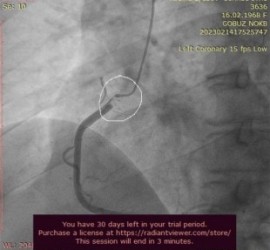

После этого случилось еще несколько подобных приступов, и каждый раз врачи разводили руками, пока в марте очередная кардиограмма действительно не показала инфаркт миокарда. Тогда женщину срочно госпитализировали и выполнили коронарографию (исследование, при котором в коронарную артерию заводится диагностический катетер, вводится контрастное вещество и выполняется серия снимков). Картина в разных проекциях менялась — в одних было видно, что есть препятствие кровотоку, на других этого препятствия не было. Врачи предположили, что у пациентки диссекция (расслоение внутренней оболочки правой коронарной артерии), и выполнили стентирование. Установленный стент должен был закрепить отслоившуюся часть артерии и прекратить приступы. Однако, вопреки ожиданиям, после стентирования женщина снова почувствовала боль.

Наиболее часто папиллярная фиброэластома крепится к аортальному клапану или к стенкам аорты на тонкой ножке, а с током крови может временно заноситься в устье коронарной артерии, прекращая кровоток по ней. При этом у больного возникают боли в груди, очень типичные для стенокардии, позже, когда опухоль покидает устье, симптомы проходят. Исследования, выполненные новгородскими врачами, несколько раз не показывали стенокардию или инфаркт именно потому, что в этот момент опухоль перемещалась и открывала кровоток.

«Внешне папиллярная фиброэластома похожа на анемоны — коралловые полипы (небольшое мягкое, пушистое образование, крепящееся на тонкой ножке). А поскольку диаметр устья коронарной артерии всего 4–5 мм, то эту «пушинку» периодически туда заносило. Она перекрывала кровоток, миокард терпел бедствие и реагировал болевым синдромом», — комментирует врач — сердечно-сосудистый хирург НМИЦ им. В. А. Алмазова Дмитрий Валериевич Бендов.